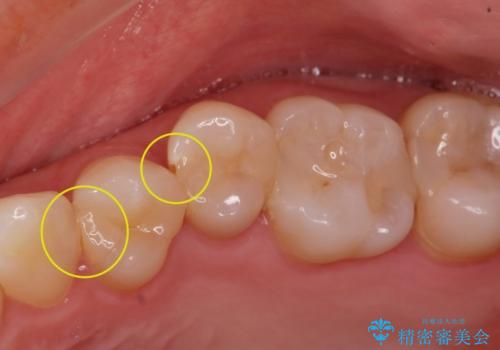

- 矯正前の患者様です。検査をしたところ虫歯が見られたので拡大鏡下で虫歯を取り除き

e-maxインレーで治療を行いました。

虫歯が多数ありましたのでまずは2本虫歯治療を行いました。